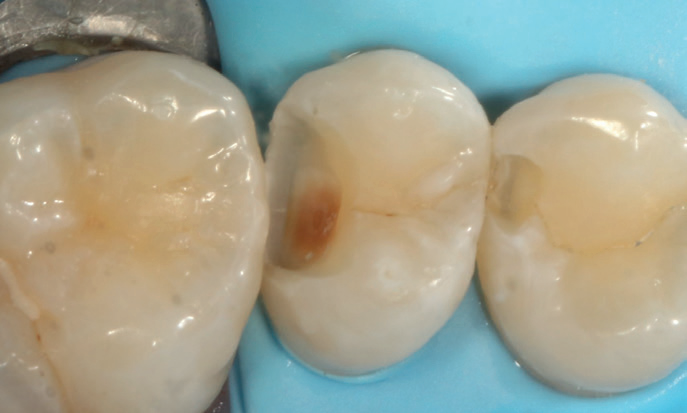

A 17-year-old female patient presented for a routine six-month examination without complaints or concerns regarding her teeth. I noted a small colour change on the upper left premolar during the examination with five times magnification loupes.

An X-ray confirmed the presence of a cavity, which was highlighted using a second-opinion AI software (Figures 1 and 2). Given the cavity’s location in the visible smile line and the patient’s age, I opted for a tooth-coloured filling rather than the NHS amalgam option. I chose Stela, a high-performance selfcure composite, for its aesthetic and functional qualities.

Figure 4: Distal caries removed UL5, distal fractured cleaner UL4